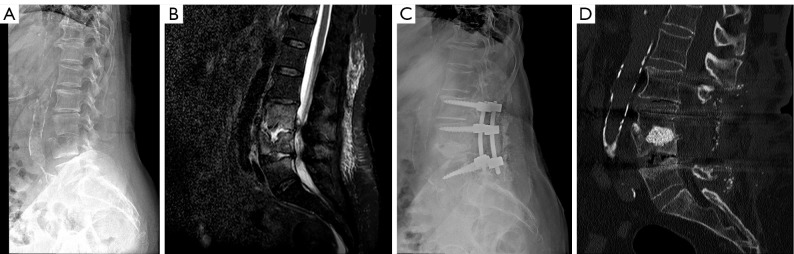

The article aims to describe the novel surgical technique of filling anterior spine cavitations in pyogenic spondylodiscitis (PS) using bioactive glass S53P4 (BAG-S53P4) (BonAlive®) in association with posterior spinal stabilization alone and its results in the first three patients. The technique starts with a posterior approach and instrumentation of the spine, total or partial laminectomy (when needed), debridement of the intervertebral space and cavity filling with BAG-S53P4, without any additional anterior instrumentation (i.e., meshes/cages). We retrospectively reviewed the first three cases of spondylodiscitis surgically treated with this technique at the department of orthopaedic surgery of the ASST-Ovest Milanese, Legnano Hospital (Italy). Functional outcomes, pain level, and C-reactive protein (CRP) trends were reported. Serial plain radiographs were collected, and a computed tomography (CT) scan was performed after a period of 2-3 years. A rapid improvement and healing from infection were observed in all cases with progressive spinal fusion and restoration of the previous quality of life. We did not observe major adverse events. BAG-S53P4 can be safely introduced in the disk space through a posterior approach to fill vertebral cavitation when the posterior wall is almost intact. It may be considered a safe and useful biomaterial in the surgical treatment of spondylodiscitis, helping in the eradication of the infection and promoting progressive spinal fusion. With this technique, anterior instrumentation and double approaches could be avoided in case of limited bone defects and moderate spinal deformity.

Abstract Image